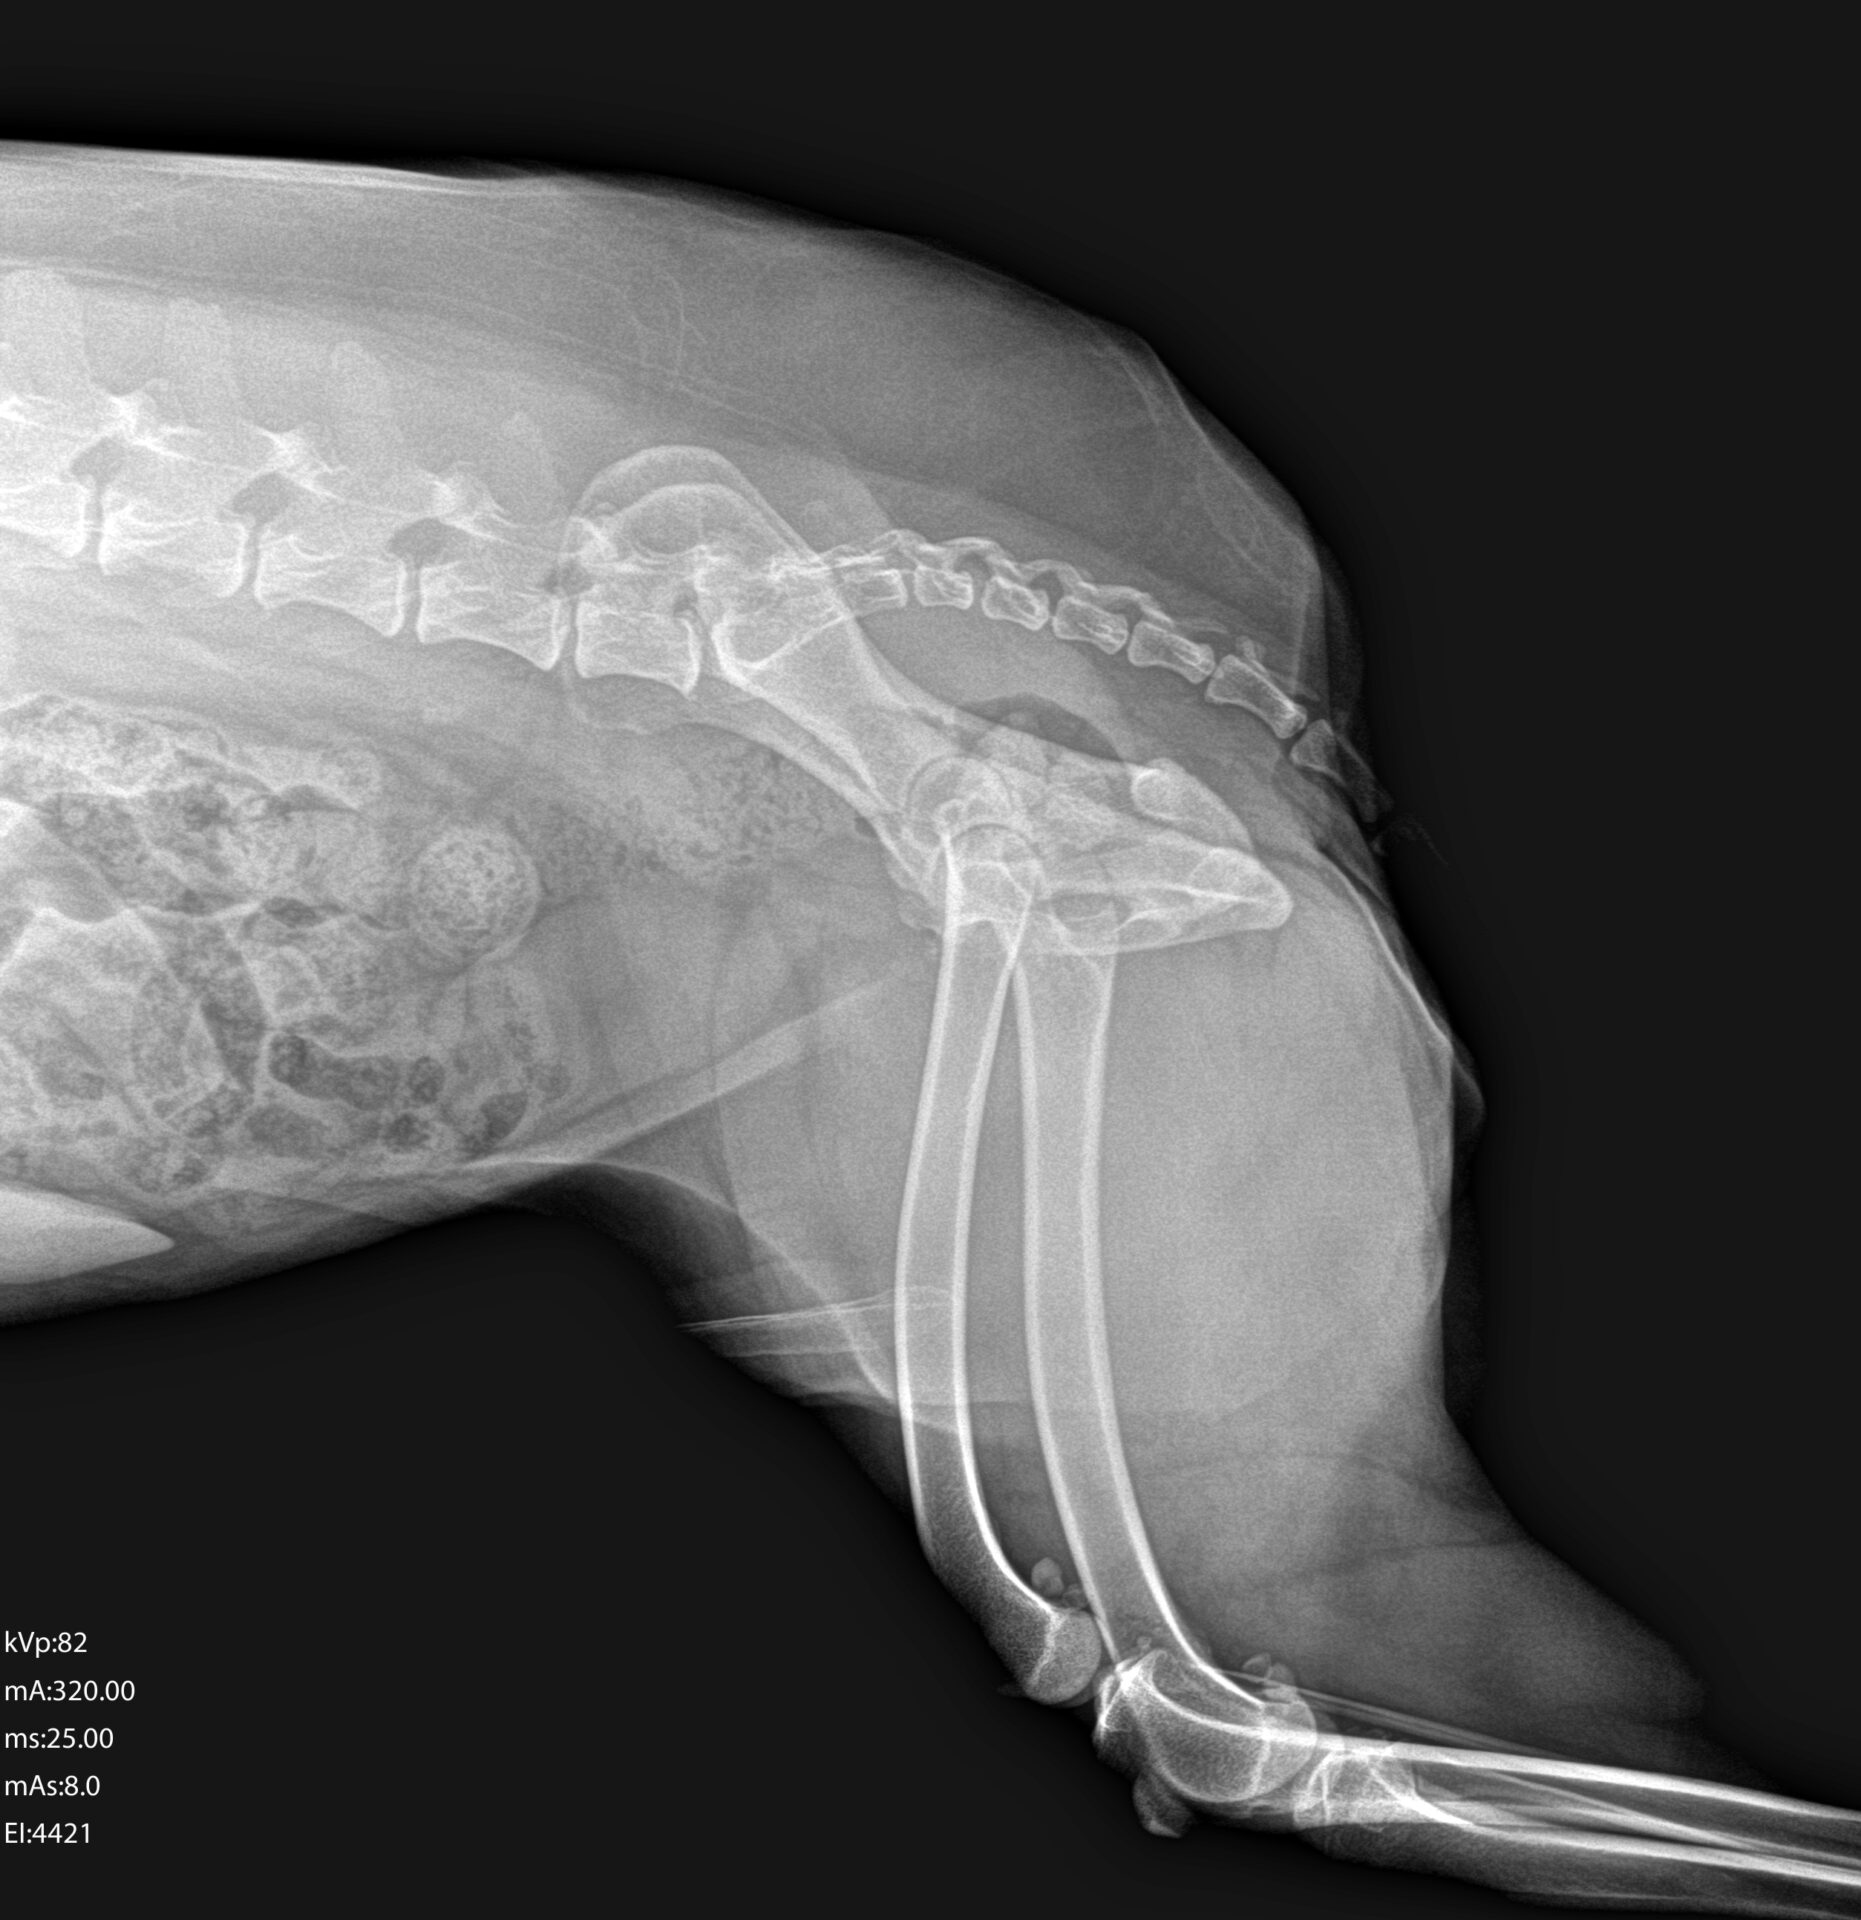

Na Prana Vet, utilizamos radiografia digital de alta qualidade para avaliar estruturas internas de forma rápida, segura e precisa.

A radiografia é uma ferramenta essencial no diagnóstico de:

- Problemas ortopédicos

- Alterações pulmonares

- Avaliação cardíaca

- Corpos estranhos

- Alterações abdominais

- Avaliação dentária e estrutural

Trabalhamos com o sistema Mindray VetiX S300, um equipamento de radiologia digital desenvolvido especificamente para medicina veterinária.

✔ Imagens de alta resolução

✔ Melhor contraste e definição

✔ Ajuste fino de parâmetros conforme o paciente

✔ Menor dose de radiação

✔ Rapidez na aquisição da imagem